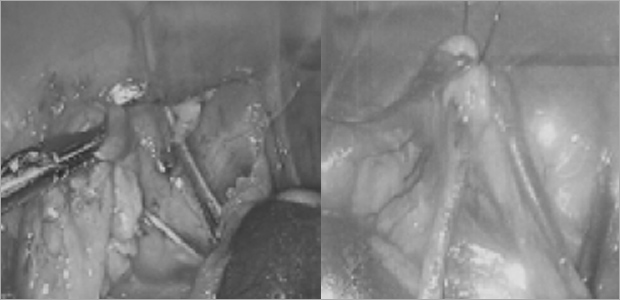

복강경 담낭절제술

케이스1

- 수술 1주차

- 수술 2주차

케이스2

- 수술 4일차

- 수술 3주차